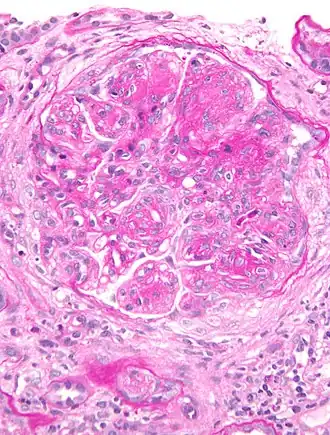

La glomérulonéphrite membranoproliférative est un type de lésion des glomérules des reins[1].

La cause peut être inconnue ou elle peut survenir à la suite d’infections, de maladies auto-immunes, d’un cancer, d’une maladie du foie ou de certains médicaments[1]. On pense que le mécanisme sous-jacent implique l'accumulation de complexes immunitaires dans les reins et l'activation du système du complément, ce qui entraîne la croissance des cellules mésangiales et l'épaississement des parois des petits vaisseaux sanguins[1].